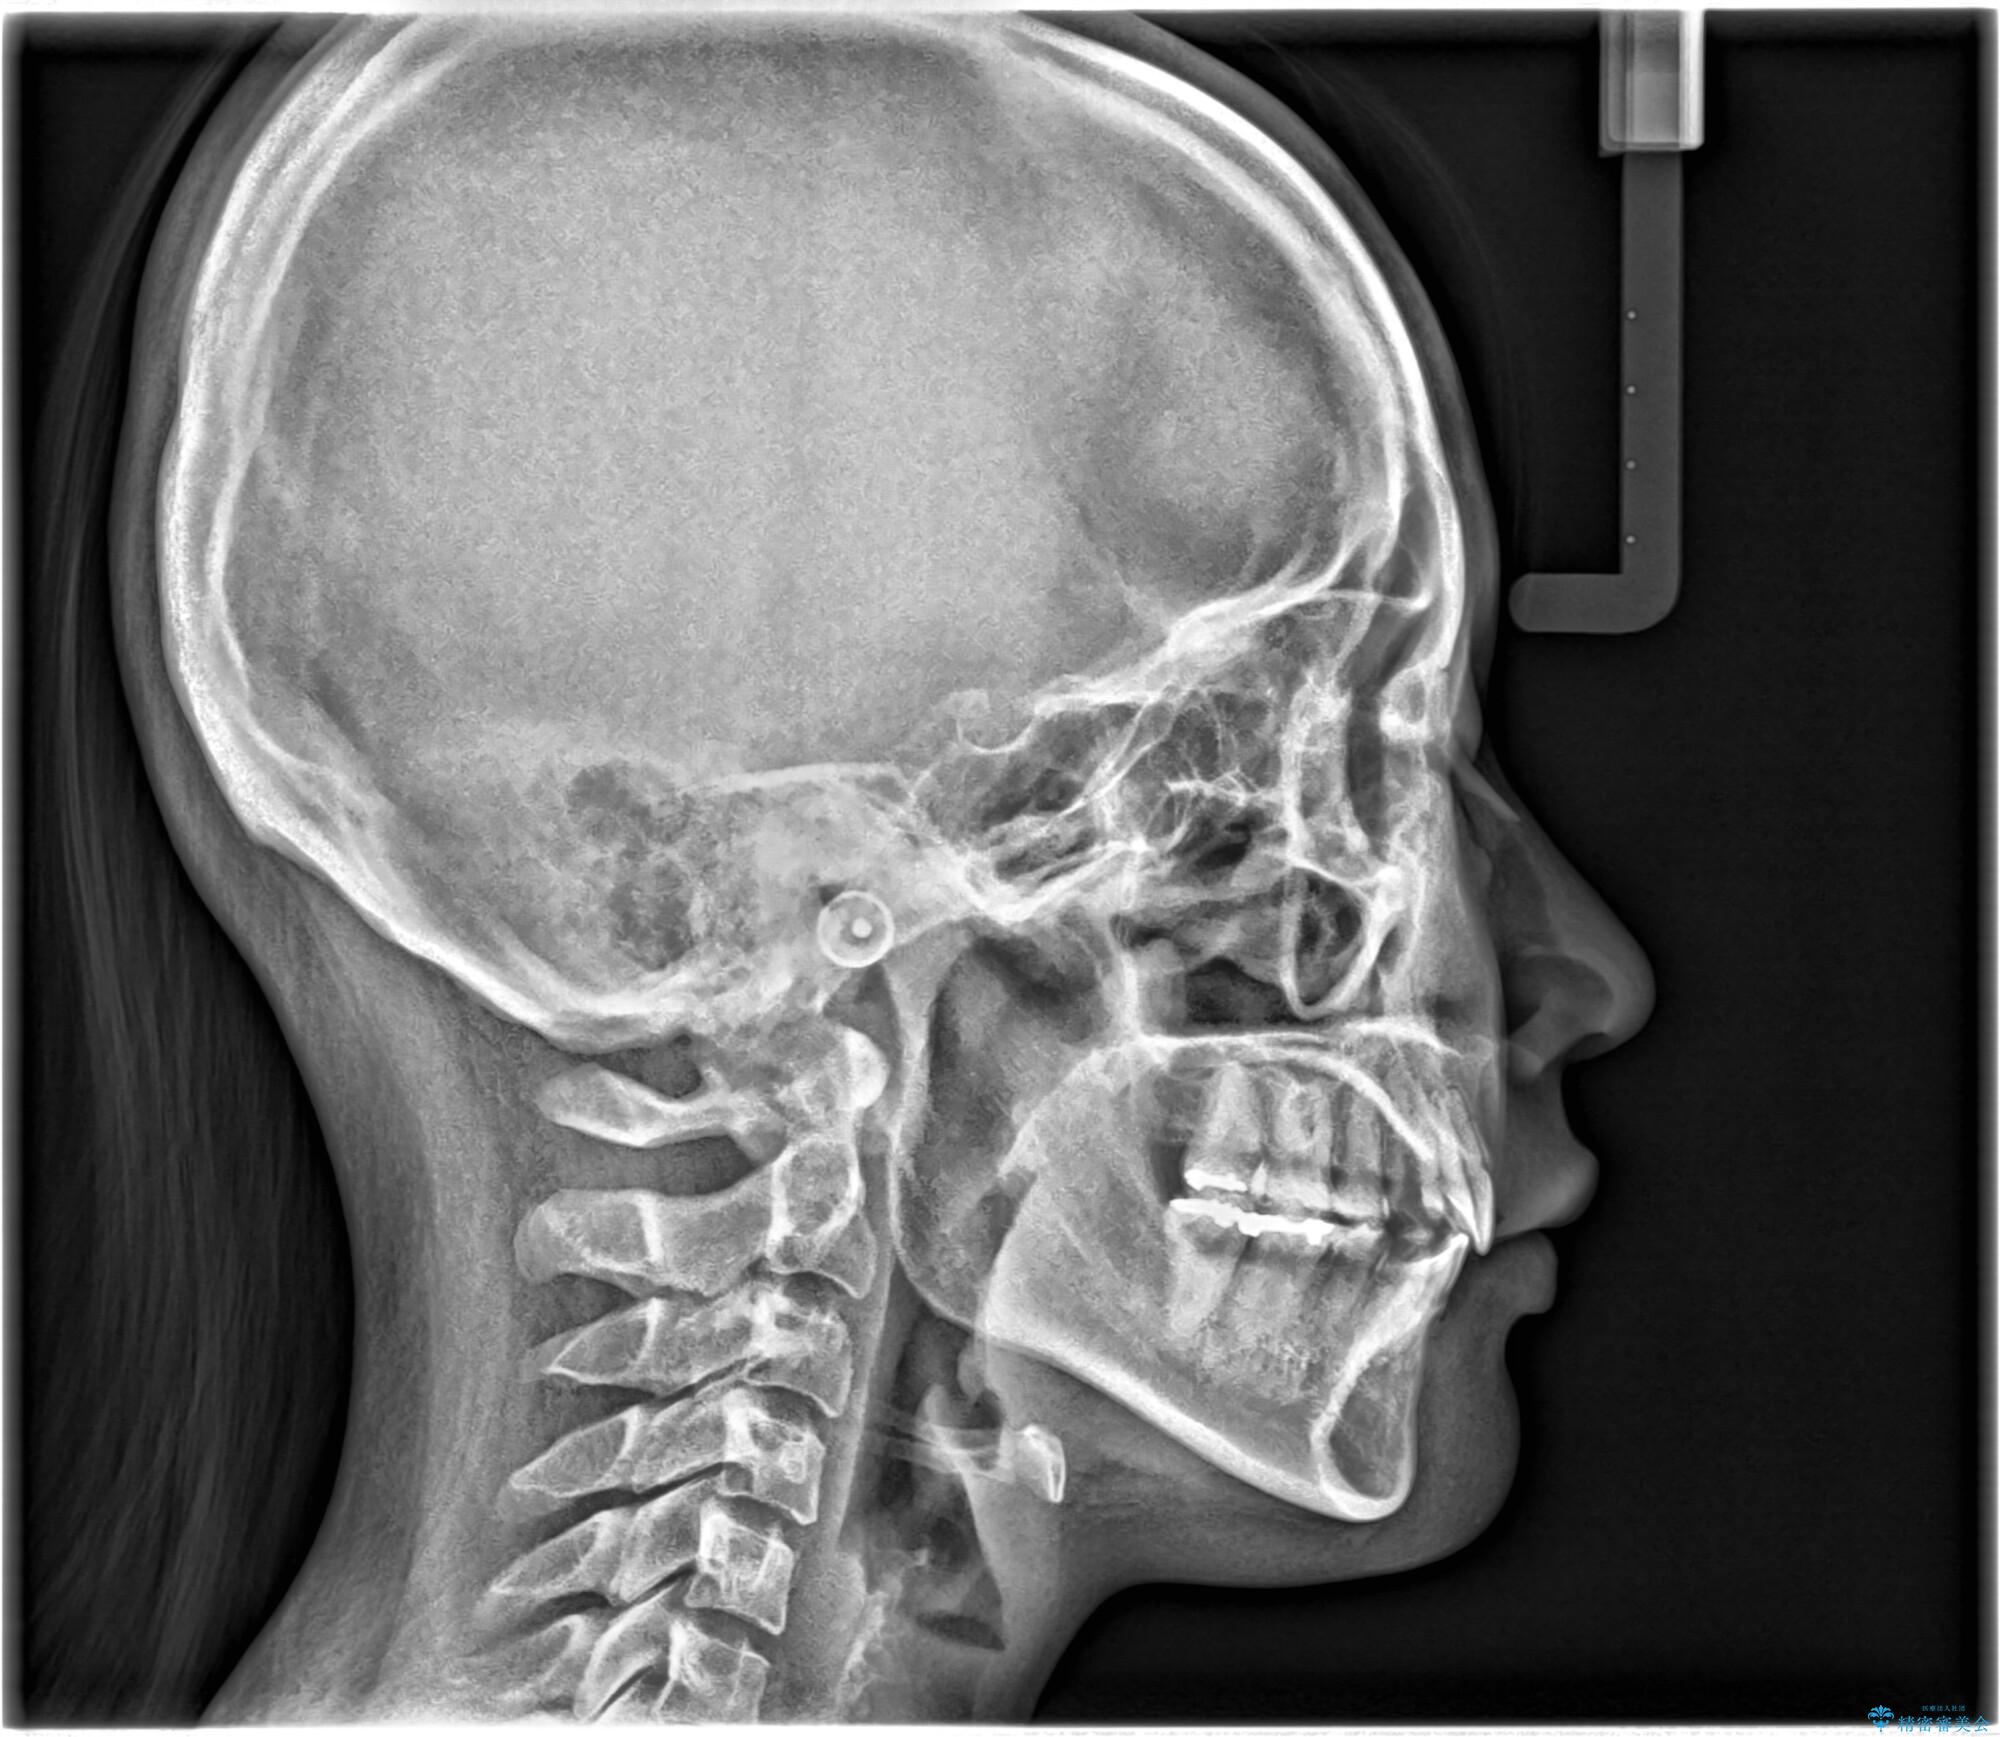

- 口元が出ていることを主訴に来院されました。

上下左右小臼歯を抜歯して審美装置で治療を行いました。

口元もスッキリと変化し、大変満足していただきました。

抜歯したスペースをきちんと下げることができるように、矯正用のアンカースクリューを用いて治療をしております。